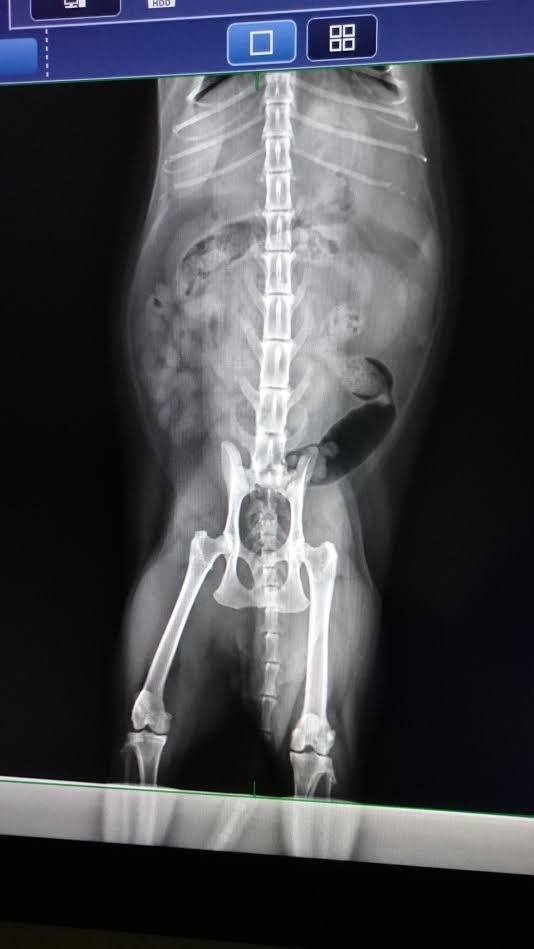

包括--照x光、看牙齒、全套血檢、照超音波、進行神經問題評估等。

106.02.02

澄諾回診 尼董 / 尼可拉斯

體重7.03Kg

尼董今日做全套血檢

照x光、超音波

輕麻,晚上6點40分先給水、7點給食物

血檢無異常,

球蛋白GLOB較高,在愛滋貓、熟齡貓身上是正常反應。

1.腳抖抖也可能是神經症狀,保養品仍再給。

2.胰臟形狀怪怪的,但胰臟炎檢驗正常,請大家再多觀察是否有嘔吐、變瘦情況,請立即回報,需安排就醫檢查。動物近況說明: 關於神經方面問題,答問紀錄如下---